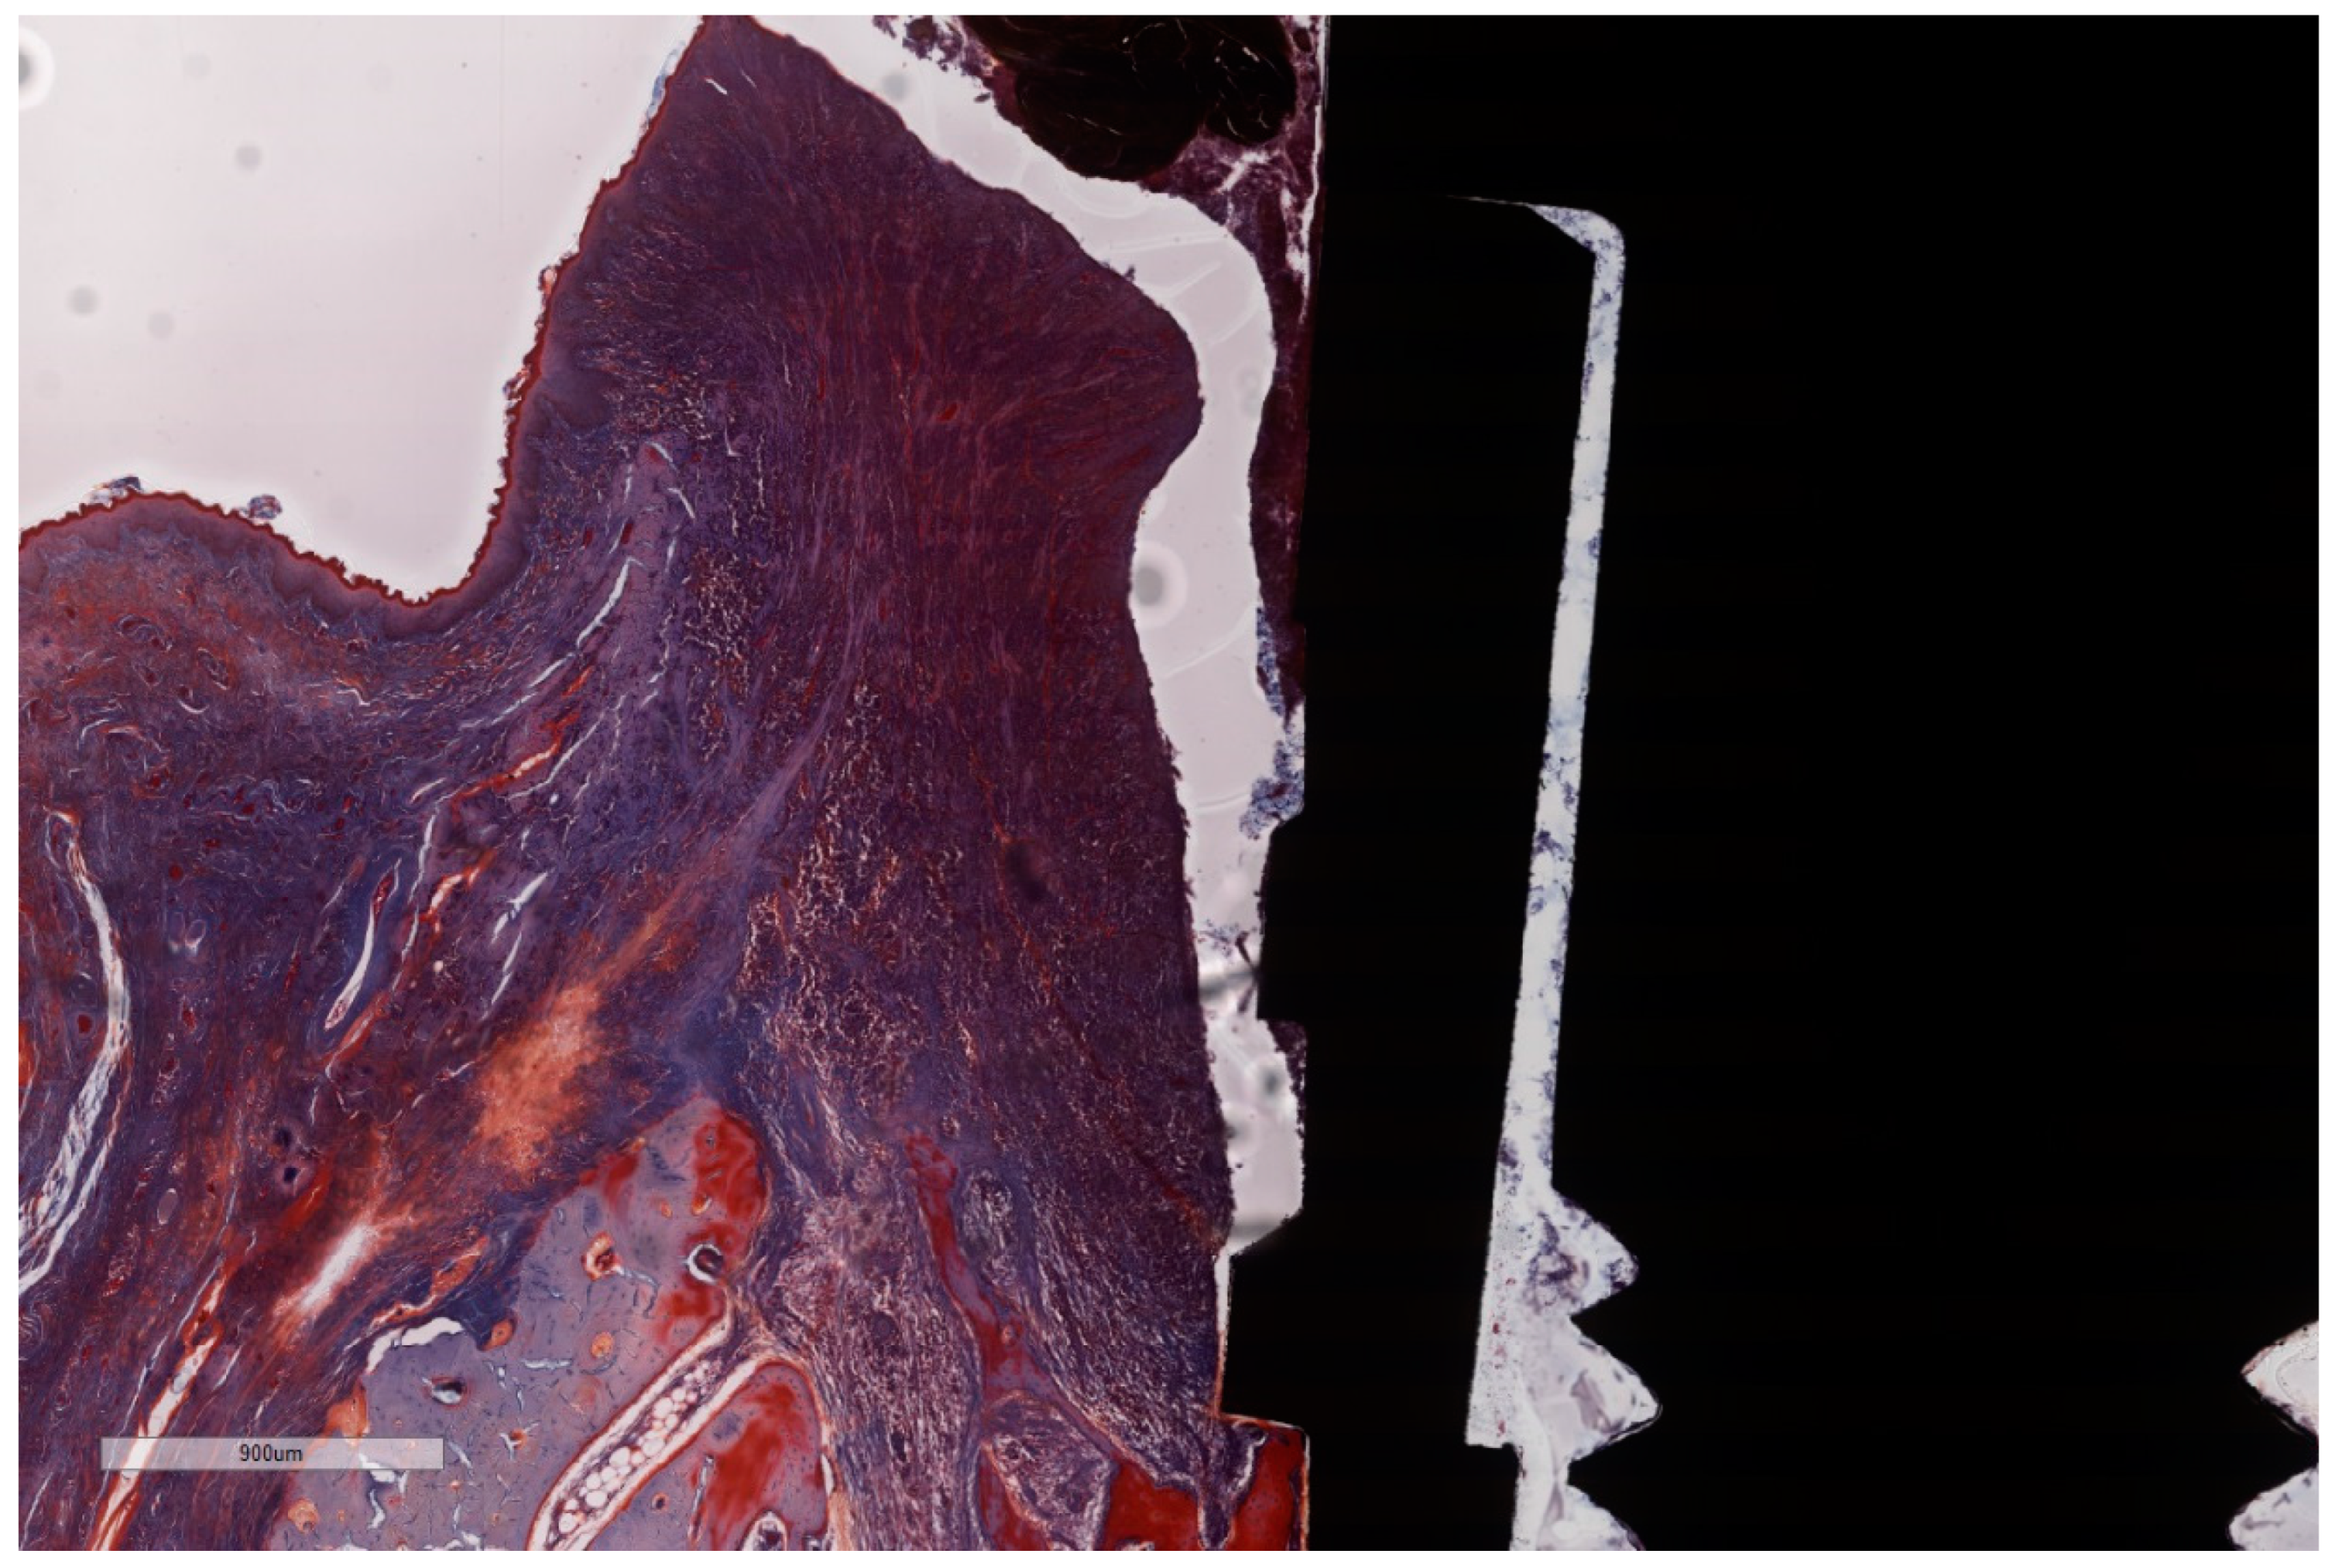

Figure 7. Histomorphometric landmarks identified on both buccal and lingual aspects in each implant: 1—implant shoulder (IS); 2—implant surface at the level of the bone crest (imp); 3—bone crest, defined as the most coronal point of the bone (BC); 4—bottom of the bone defect (BD); 5—margin of the peri-implant mucosa (PM); 6—the apical termination of the junctional epithelium (aJE); 7—the coronal level of the infiltrated connective tissue (cICT); 8—the apical extension of the infiltrated connective tissue (aICT); 9—the most apical extension of the submarginal biofilm that was interposed between the implant and the pocket epithelium of the peri-implant mucosa (aPlaque). (Implant #5, mirroring sections, (A)—Masson Goldner Anilin blue stain, (B)—Movat Pentachrome stain, original magnification ×2).

3.2. Histometric Findings

Due to the particularities of the MGA and MOV stainings, some measurements succeeded better on MGA than on MOV sections (Figure 7A,B). Moreover, artifacts resulting from the cutting–grinding process necessitated the complementing of measurements on both stainings in order to obtain values as accurate as possible.